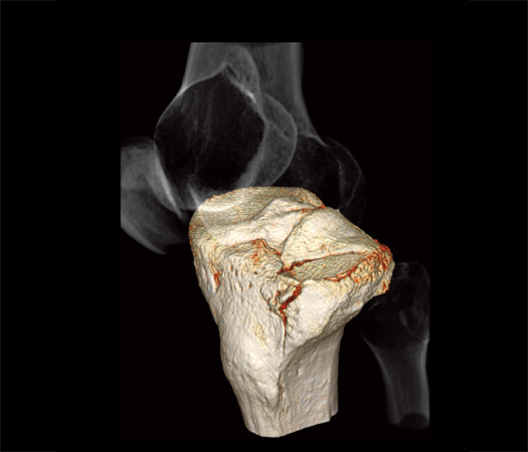

Fractura de meseta tibial